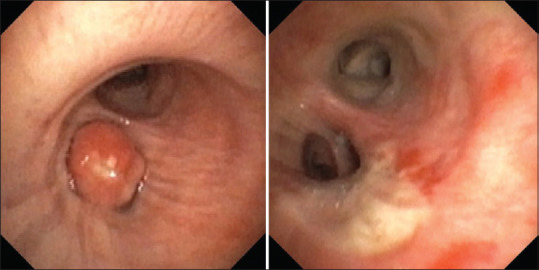

摘要错构瘤是一种常见的肺良性肿瘤。虽然大多数肺错构瘤位于肺实质内,但很少表现为支气管内肿瘤。我们描述了一例75岁的男性通过传统的柔性支气管镜切除支气管内错构瘤,另一例55岁的男性通过机器人导航支气管镜诊断支气管内错构瘤。我们还描述了过去13年中在我们机构诊断的支气管内错构瘤的其他三个病例的显著特征。随着先进的导航支气管镜技术的出现,我们预测支气管内错构瘤的鉴别率将会增加。

Abstract: Hamartoma is a common benign tumour of the lung. Although most pulmonary hamartomas are located within the lung parenchyma, rarely they present as endobronchial tumours. We are describing one case of a 75-year-old gentleman with endobronchial hamartoma removed via traditional flexible bronchoscopy and another case of a 55-year-old gentleman whose endobronchial hamartoma was diagnosed via robotic navigational bronchoscopy. We are also describing the salient features of three other cases of endobronchial hamartoma diagnosed at our institution in the last 13 years. With the emergence of advanced navigational bronchoscopy techniques, we predict that the incidence of identifying endobronchial hamartomas will increase.